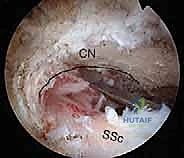

2. إحداث الثقوب (Portals) واستكشاف المفصل

يقوم الدكتور هطيف بعمل 3 إلى 4 ثقوب صغيرة جداً حول الكتف. يُدخل كاميرا المنظار (Arthroscope) لعمل جولة استكشافية شاملة لداخل المفصل، وتقييم الغضاريف، أوتار الكفة المد